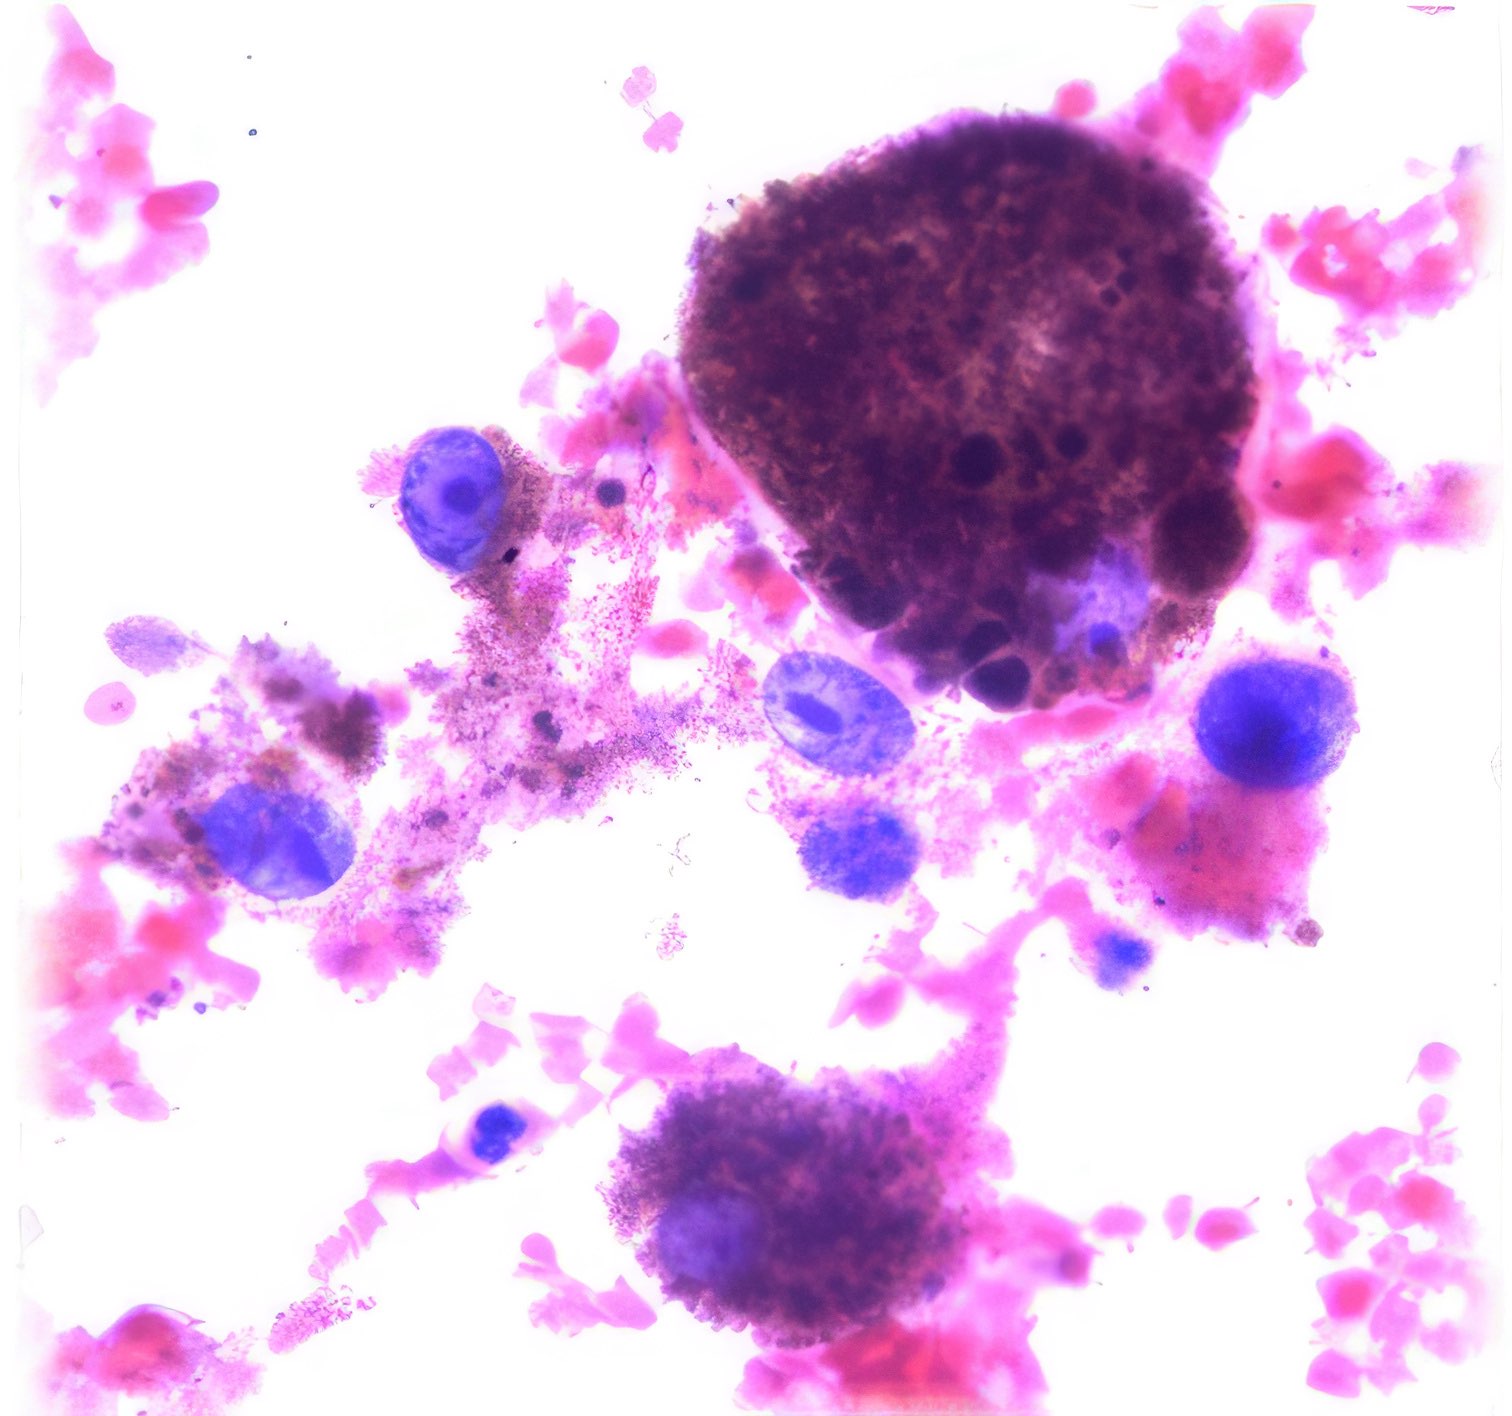

M, 55 Jahre, bemerkte seit 3 Monaten eine zunehmende inguinale Lymphknotenschwellung, der größte 3 x 4 cm messend, davon Feinnadelaspiration (FNA). Abbildung 1 bis 4: Verschiedene Areale des zytologischen Ausstrichs. Orig. 63x

Beschreibung

Die Bilder zeigen hochatypische Zellen. Deren überwiegend runde, teils auch ovalen Kerne variieren erheblich in ihrer Größe, sind deutlich grob strukturiert und enthalten meist ein oder mehrere prominente Nukleolen bzw. Chromozentren. Das Zytoplasma erscheint fragil. In jedem Bild finden sich auch Zellen mit pigmentbeladenem Zytoplasma. Der Ausstrichhintergrund enthält Blut und Zelldetritus, ebenfalls vermischt mit Pigmentkörnchen.

Kommentar

Der Patient beobachtete seit einem Jahr am Fuß eine pigmentierte Veränderung, die seit 3 Monaten auf 3 cm Durchmesser zunahm. Die prominente Atypie und die pigmenthaltigen Zellen sowie die ausgedehnte Metastasierung in die inguinalen Lymphknoten sind typisch für das Melanom. Eine Verwechslung des Melanin-Pigments mit Hämosiderin ist wegen der Zellatypie so gut wie ausgeschlossen. – Amelanotische Melanome zeigen oft eine weniger ausgeprägte Kernatypie und sind eher mit einem anderen Tumor zu verwechseln.